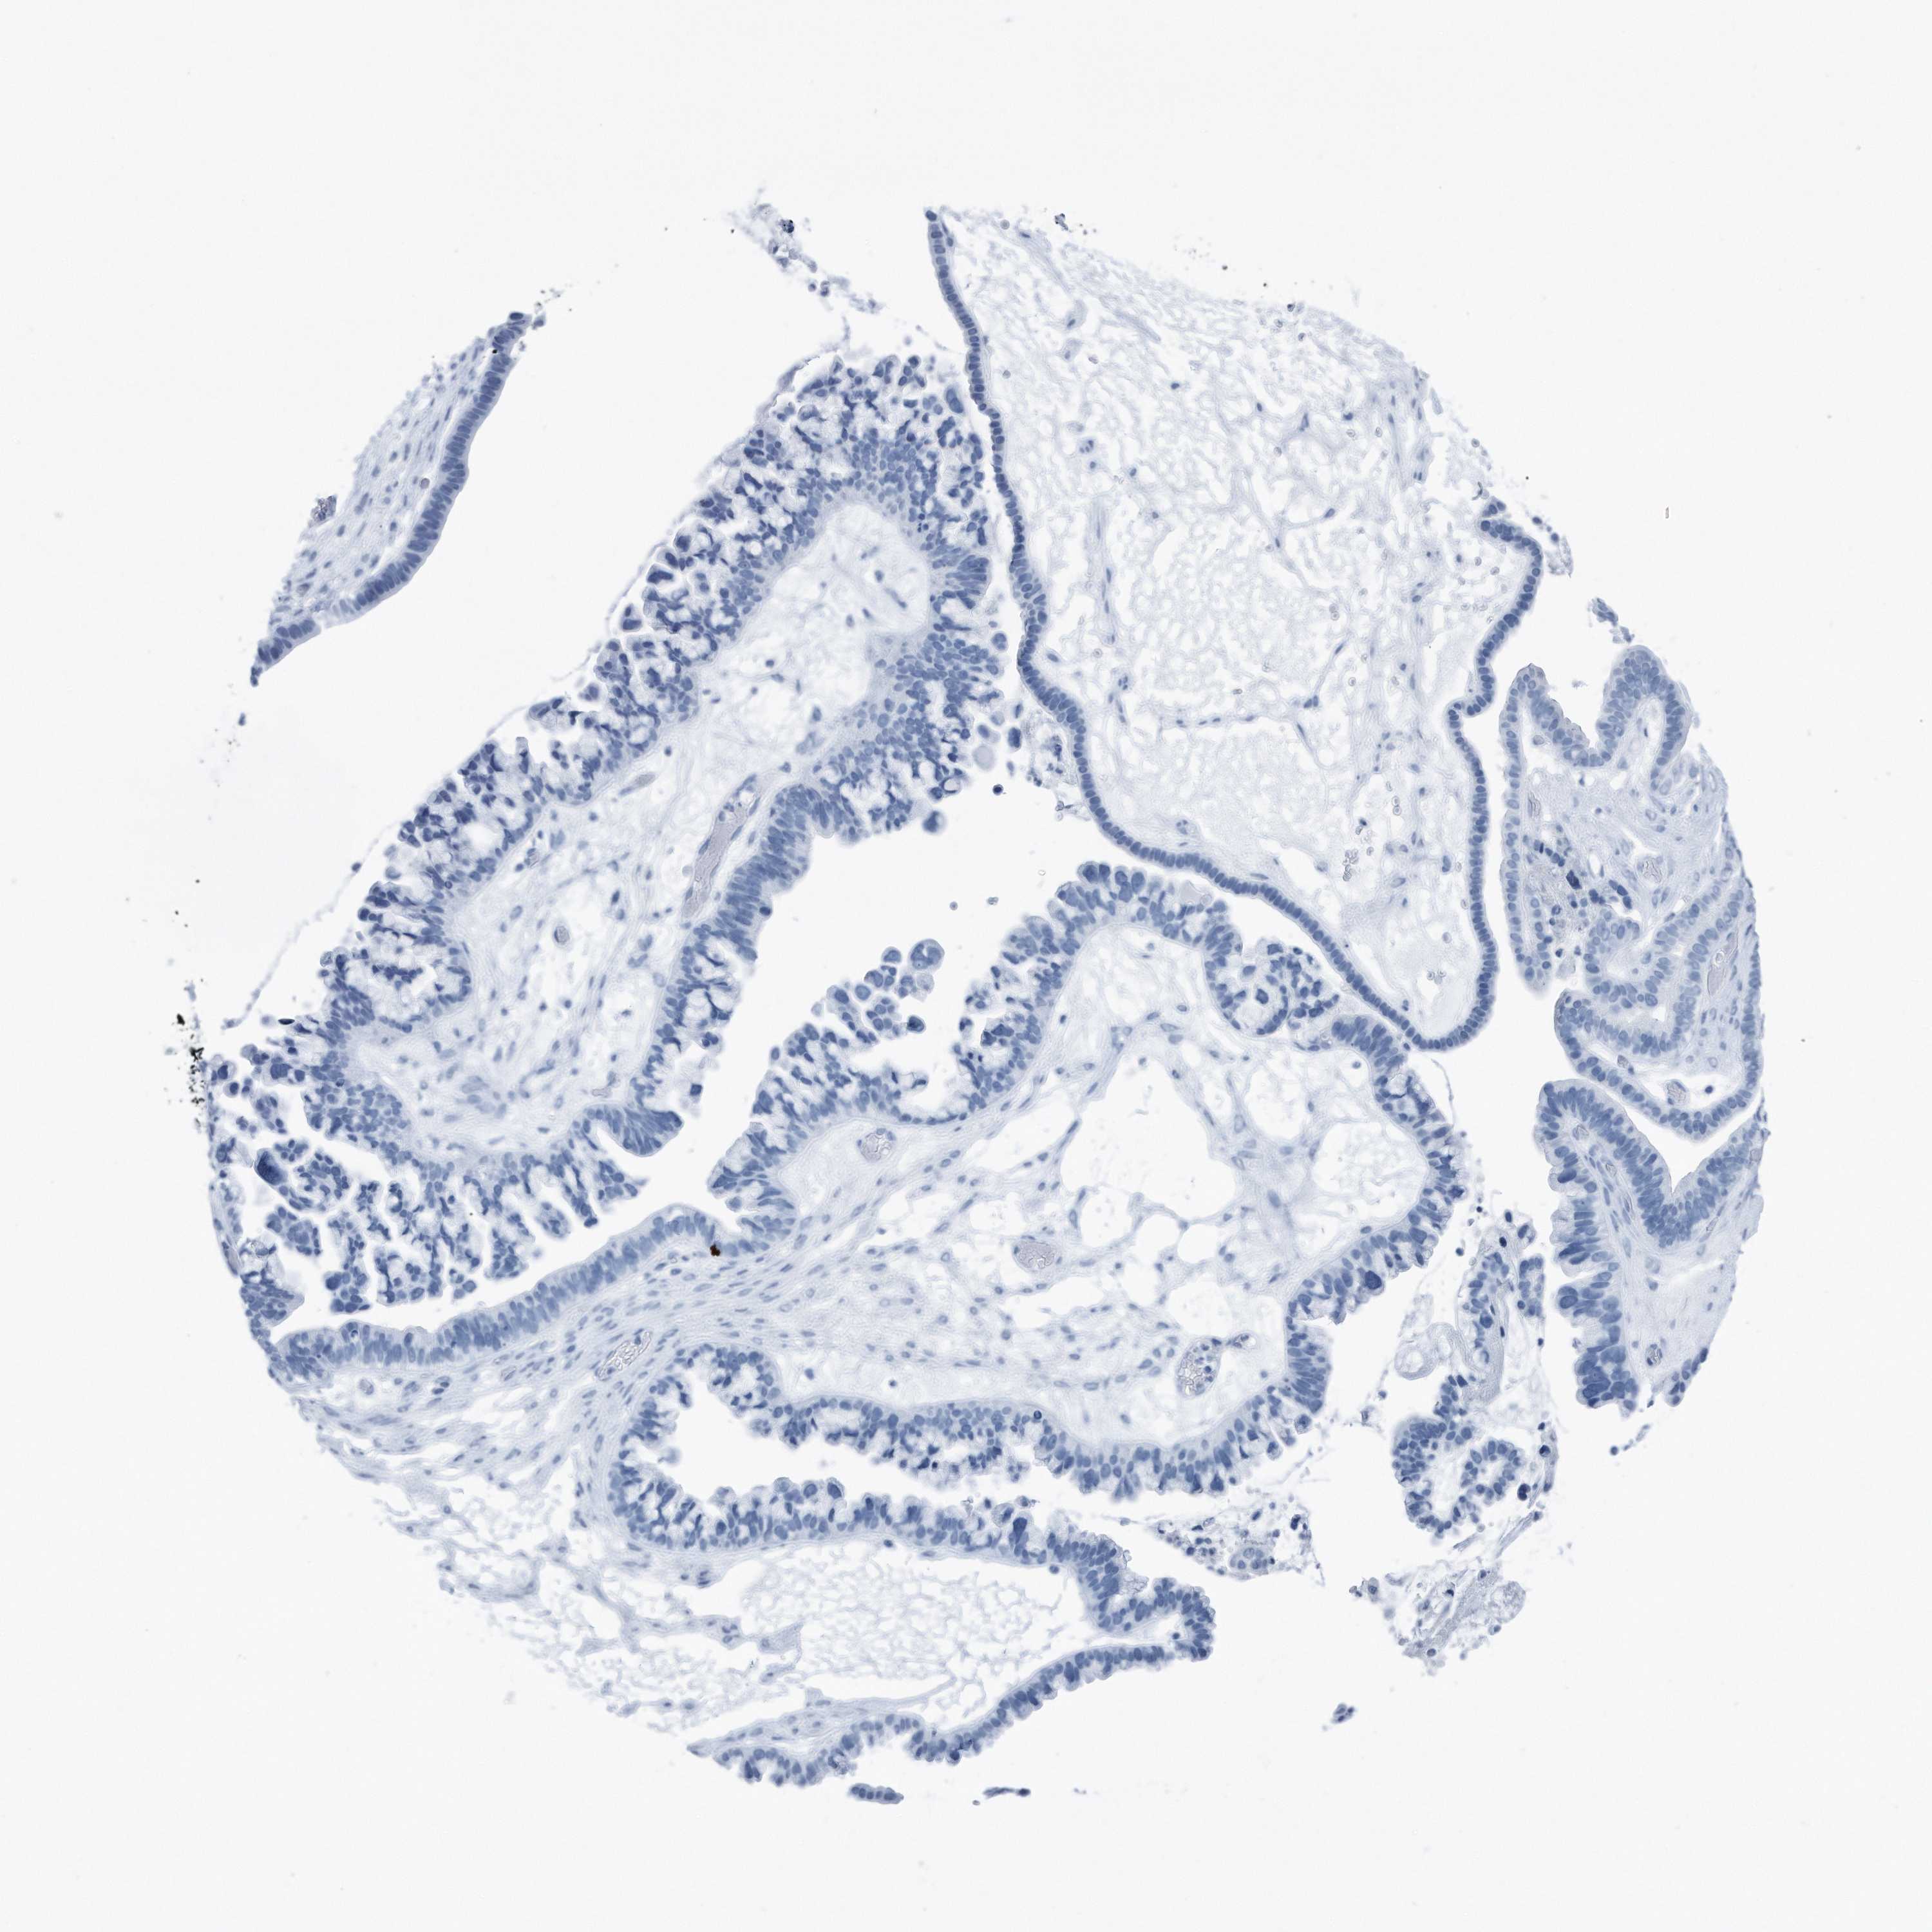

OVARIAN CANCER - Protein expressioni

A mouse-over function shows sample information and annotation data. Click on an image to view it in a full screen mode. Samples can be filtered based on level of antibody staining by selecting one or several of the following categories: high, medium, low and not detected. The assay and annotation is described here.

Note that samples used for immunohistochemistry by the Human Protein Atlas do not correspond to samples in the TCGA dataset.

Antibody stainingi

Antibody staining in the annotated cell types in the current human tissue is reported as not detected, low, medium, or high, based on conventional immunohistochemistry profiling in selected tissues. This score is based on the combination of the staining intensity and fraction of stained cells.

Each image is clickable and will lead to virtual microscopy that enables deeper exploration of all samples and also displays staining intensity scores, fraction scores and subcellular localization as well as patient and tissue information for each sample.

Antibody HPA030147

Staining

High

Medium

Low

Not detected

Intensity

Strong

Moderate

Weak

Negative

Quantity

>75%

75%-25%

<25%

None

Location

Nuclear

Cytoplasmic/membranous

Cytoplasmic/membranous,nuclear

Cystadenocarcinoma, serous, NOS

Carcinoma, endometroid

Cystadenocarcinoma, mucinous, NOS

Carcinoma, NOS